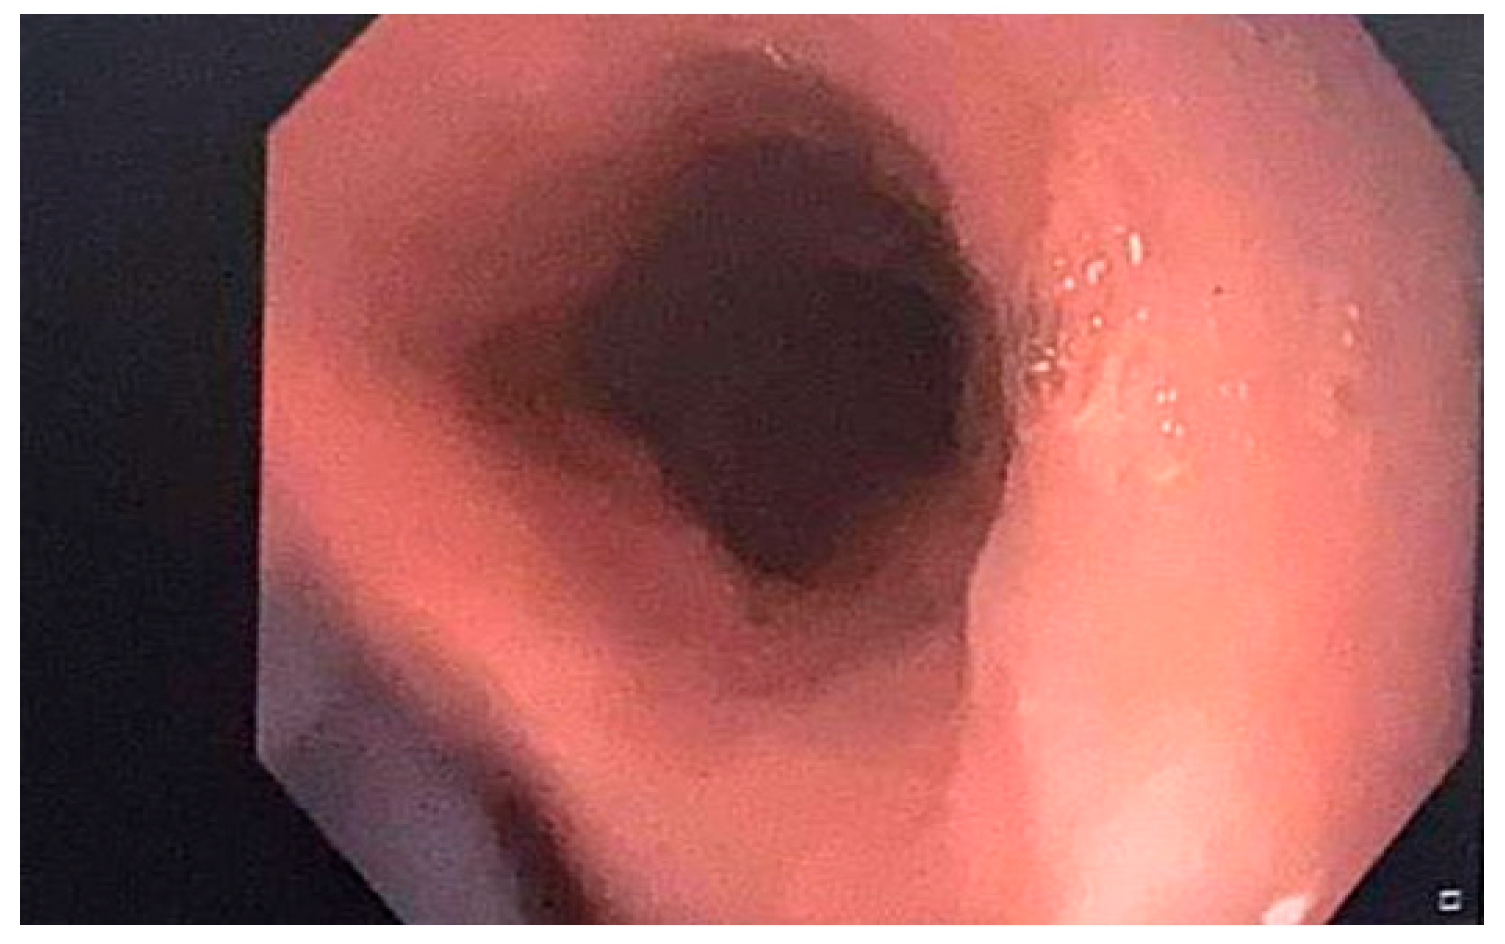

Apixaban-Induced Esophagitis Dissecans Superficialis-Case Report and Literature Review

2. Case Presentation